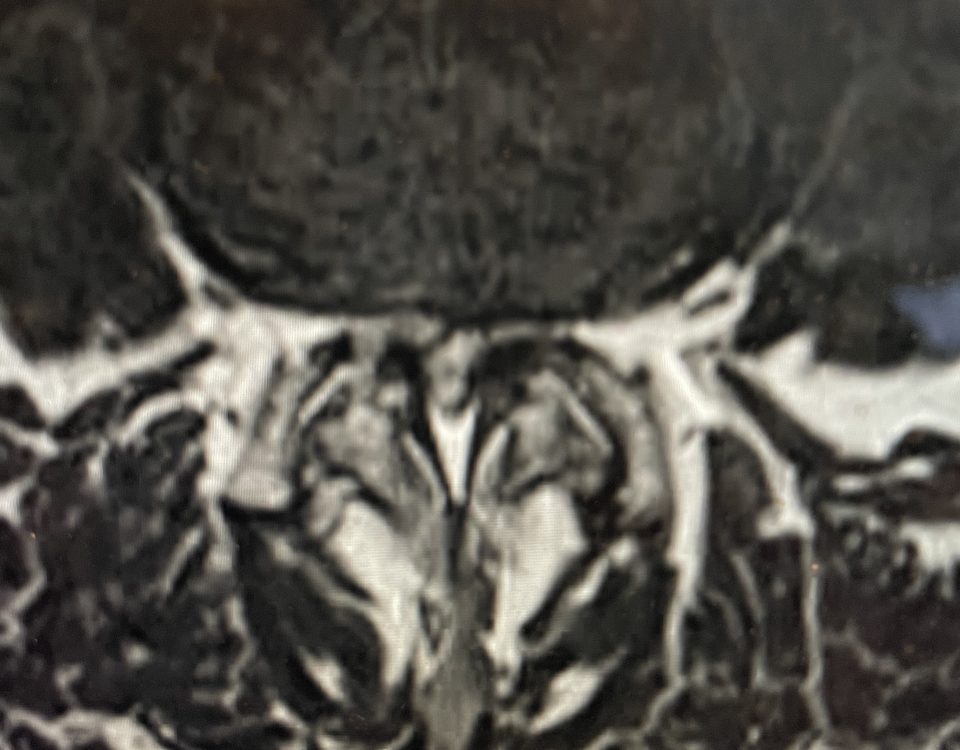

The actual structural cause of lumbar thecal sac compression can vary in degenerative spondylolisthesis and stenosis. The culprits are commonly thickened ligamentum flavum or severe facet […]

After 25 years in practice, I still find it challenging, but quite rewarding: removing degenerative material off the dural membrane in the lumbar spine. Some people […]

Nervous tissue is soft. The thecal sac is surrounded by a rigid bony ring which forms the spinal canal. Any mass that fills the very small […]